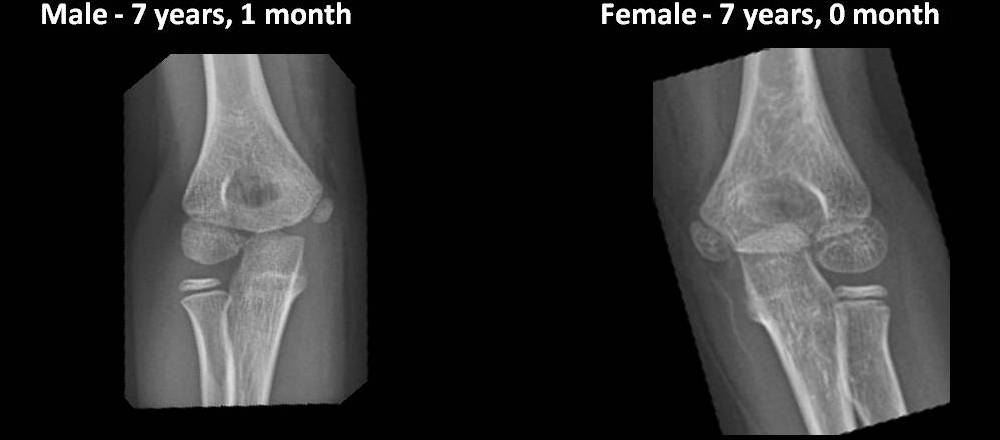

Elbow Ossification Centers

The ages at which the elbow ossification centers appear are highly variable. There is marked gender difference with girls developing up to 2 years before boys. However, the order of appearance of the ossification centers is highly reliable and follows the CRITOE mnemonic: Capitulum, Radial head, medial (Internal) epicondyle, Trochlea, Olecranon, and lateral (External) epicondyle. Pay attention to the appearance and maturation of the normal ossification centers as you scroll through the images below.

*Each image in this exhibit represents a unique patient radiographed at CHP of UPMC between 07/01/12 and 06/30/13